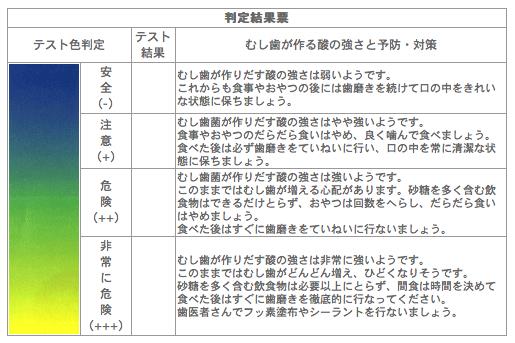

みなさん、こんにちは。川西歯科医院 埋見真紀です。 今日はむし歯菌検査についてお話します。 この検査はむし歯菌が作り出す酸の強さを調べる検査です。...